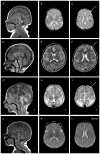

Lissencephaly ("smooth brain," LIS) is a malformation of cortical development associated with deficient neuronal migration and abnormal formation of cerebral convolutions or gyri. The LIS spectrum includes agyria, pachygyria, and subcortical band heterotopia. Our first classification of LIS and subcortical band heterotopia (SBH) was developed to distinguish between the first two genetic causes of LIS-LIS1 (PAFAH1B1) and DCX. However, progress in molecular genetics has led to identification of 19 LIS-associated genes, leaving the existing classification system insufficient to distinguish the increasingly diverse patterns of LIS. To address this challenge, we reviewed clinical, imaging and molecular data on 188 patients with LIS-SBH ascertained during the last 5 years, and reviewed selected archival data on another ∼1,400 patients. Using these data plus published reports, we constructed a new imaging based classification system with 21 recognizable patterns that reliably predict the most likely causative genes. These patterns do not correlate consistently with the clinical outcome, leading us to also develop a new scale useful for predicting clinical severity and outcome. Taken together, our work provides new tools that should prove useful for clinical management and genetic counselling of patients with LIS-SBH (imaging and severity based classifications), and guidance for prioritizing and interpreting genetic testing results (imaging based- classification).